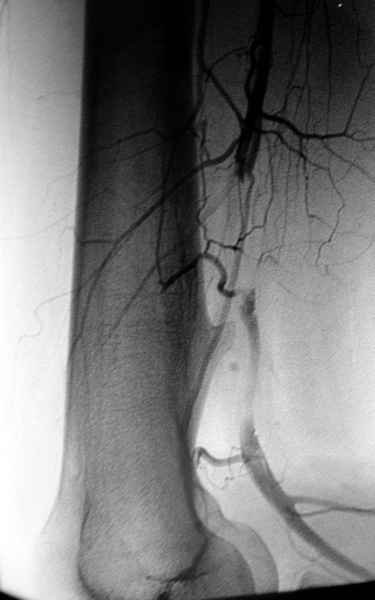

áÎÇÉÏÇÒÁÆÉÑ ÐÏÄÔ×ÅÒÄÉÌÁ ×ÁÓËÕÌÑÒÎÕÀ ÁÎÅ×ÒÉÚÍÕ × ÒÅÚÕÌØÔÁÔÅ ÄÁ×ÌÅÎÉÑ

ÜËÚÏÓÔÏÚÏÍ. óÏ×ÍÅÓÔÎÏ Ó ÓÏÓÕÄÉÓÔÙÍ ÈÉÒÕÒÇÏÍ ÂÙÌÁ ÐÒÏ×ÅÄÅÎÁ

ÐÌÏÓËÏÓÔÎÁÑ ÒÅÚÅËÃÉÑ Ó ÄÁÌØÎÅÊÝÉÍ ×ÏÓÓÔÁÎÏ×ÌÅÎÉÅÍ ÓÏÓÕÄÁ ×ÅÎÏÚÎÙÍ

ÇÒÁÆÔÏÍ.

éÍÑ     : #2 angiogram.jpg

ôÉÐ     : image/jpeg

òÁÚÍÅÒ  : 24886 ÂÁÊÔÏ×

ïÐÉÓÁÎÉÅ: ÏÔÓÕÔÓÔ×ÕÅÔ

Url     : http://weborto.net:8080/pipermail/ortho/attachments/20080403/4b5e6a95/attachment-0006.jpg